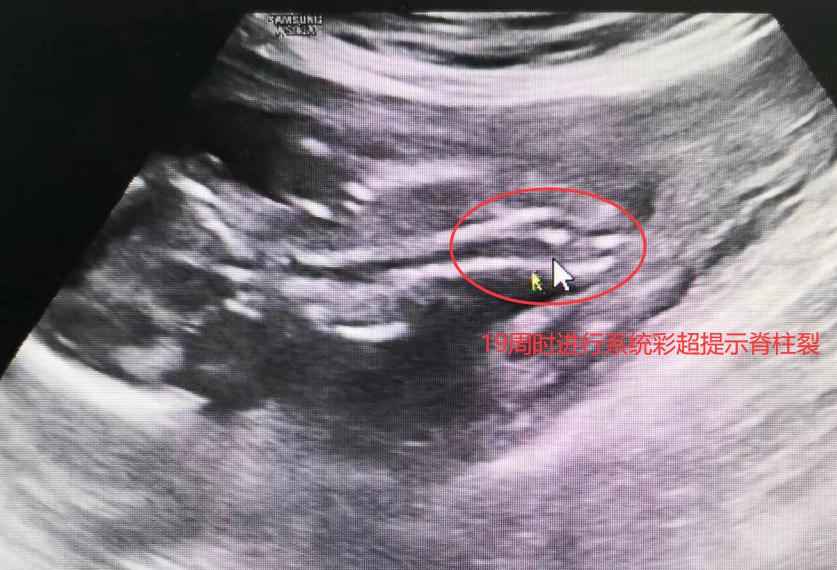

而另外一名孕妈妈李女士(化名)在做NT的时候已提示存在异常风险,可李女士想再坚持一下。在孕近5个月(19周)进行系统彩超检查的时候再次提示其中一个胎儿脊柱裂结构异常,好在另一个胎儿目前是正常的。经多家医院系统B超均证实双胎之一胎儿畸形后,李女士同样在桂林市妇幼保健院接受了减胎术,目前随访母胎良好。